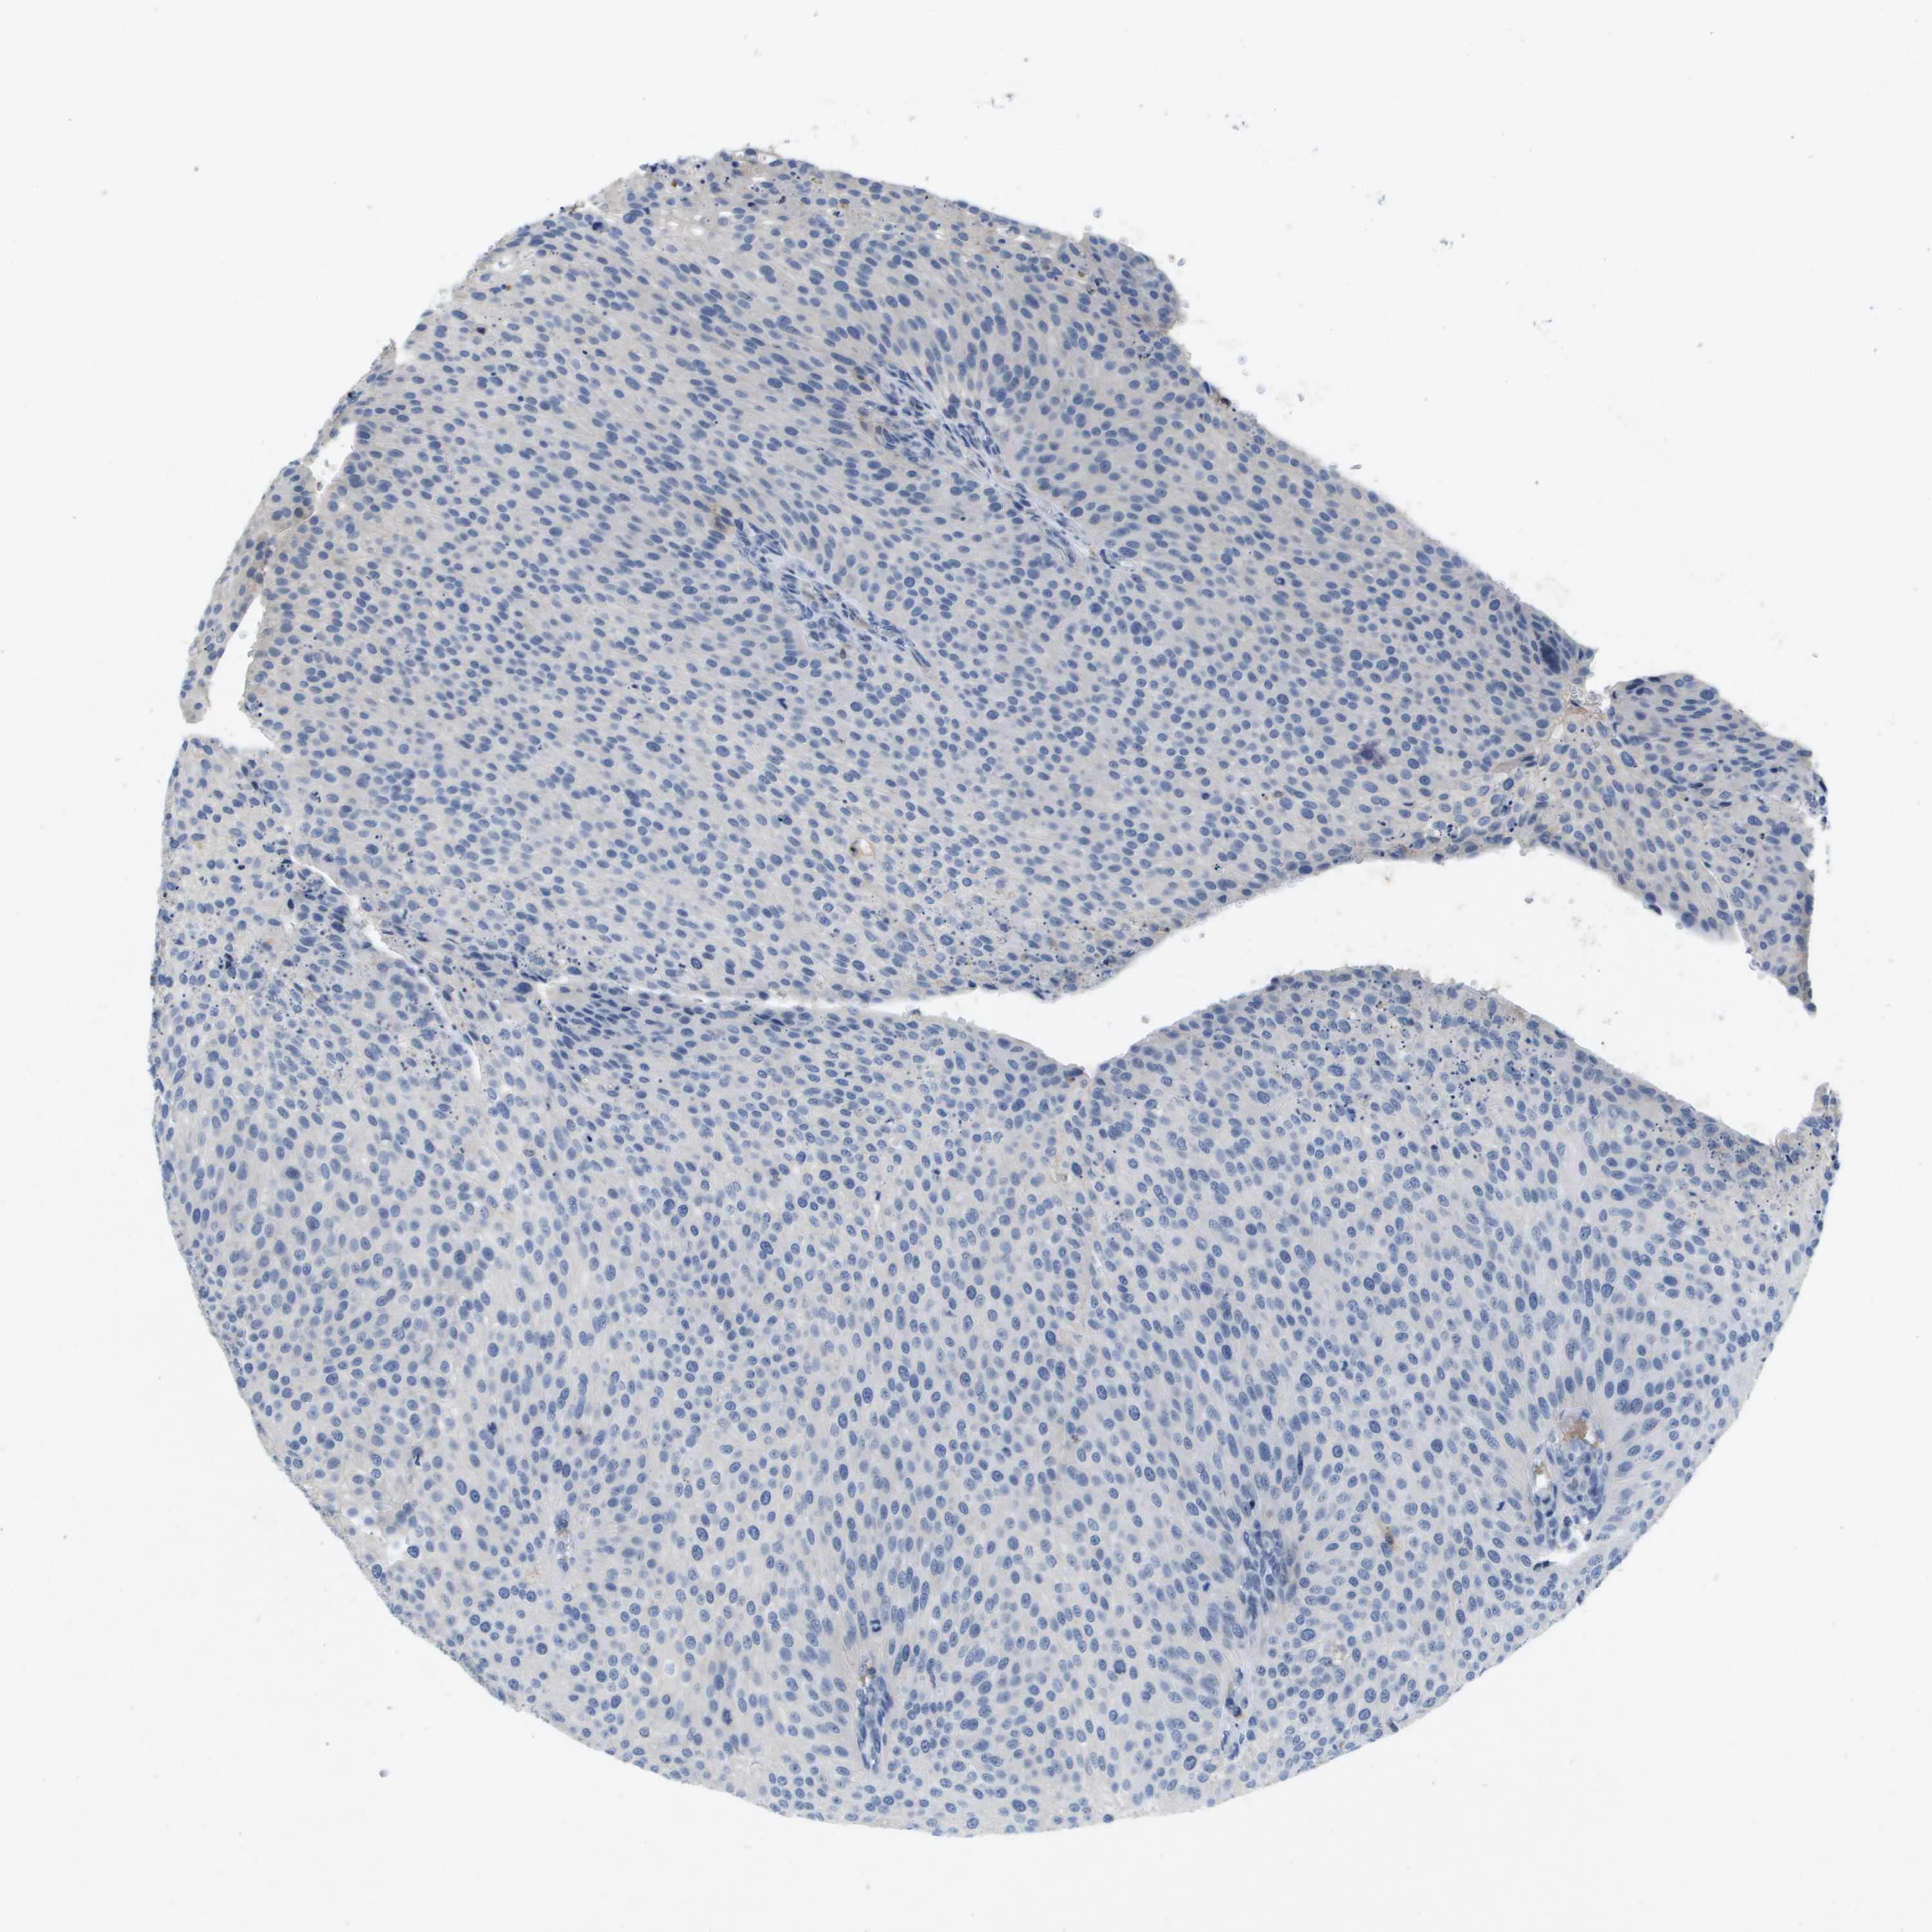

UROTHELIAL CANCER - Protein expressioni

A mouse-over function shows sample information and annotation data. Click on an image to view it in a full screen mode. Samples can be filtered based on level of antibody staining by selecting one or several of the following categories: high, medium, low and not detected. The assay and annotation is described here.

Note that samples used for immunohistochemistry by the Human Protein Atlas do not correspond to samples in the TCGA dataset.

Antibody stainingi

Antibody staining in the annotated cell types in the current human tissue is reported as not detected, low, medium, or high, based on conventional immunohistochemistry profiling in selected tissues. This score is based on the combination of the staining intensity and fraction of stained cells.

Each image is clickable and will lead to virtual microscopy that enables deeper exploration of all samples and also displays staining intensity scores, fraction scores and subcellular localization as well as patient and tissue information for each sample.

Antibody HPA016966

Staining

High

Medium

Low

Not detected

Intensity

Strong

Moderate

Weak

Negative

Quantity

>75%

75%-25%

<25%

None

Location

Nuclear

Cytoplasmic/membranous

Cytoplasmic/membranous,nuclear

Urothelial carcinoma, Low grade

Urothelial carcinoma, High grade